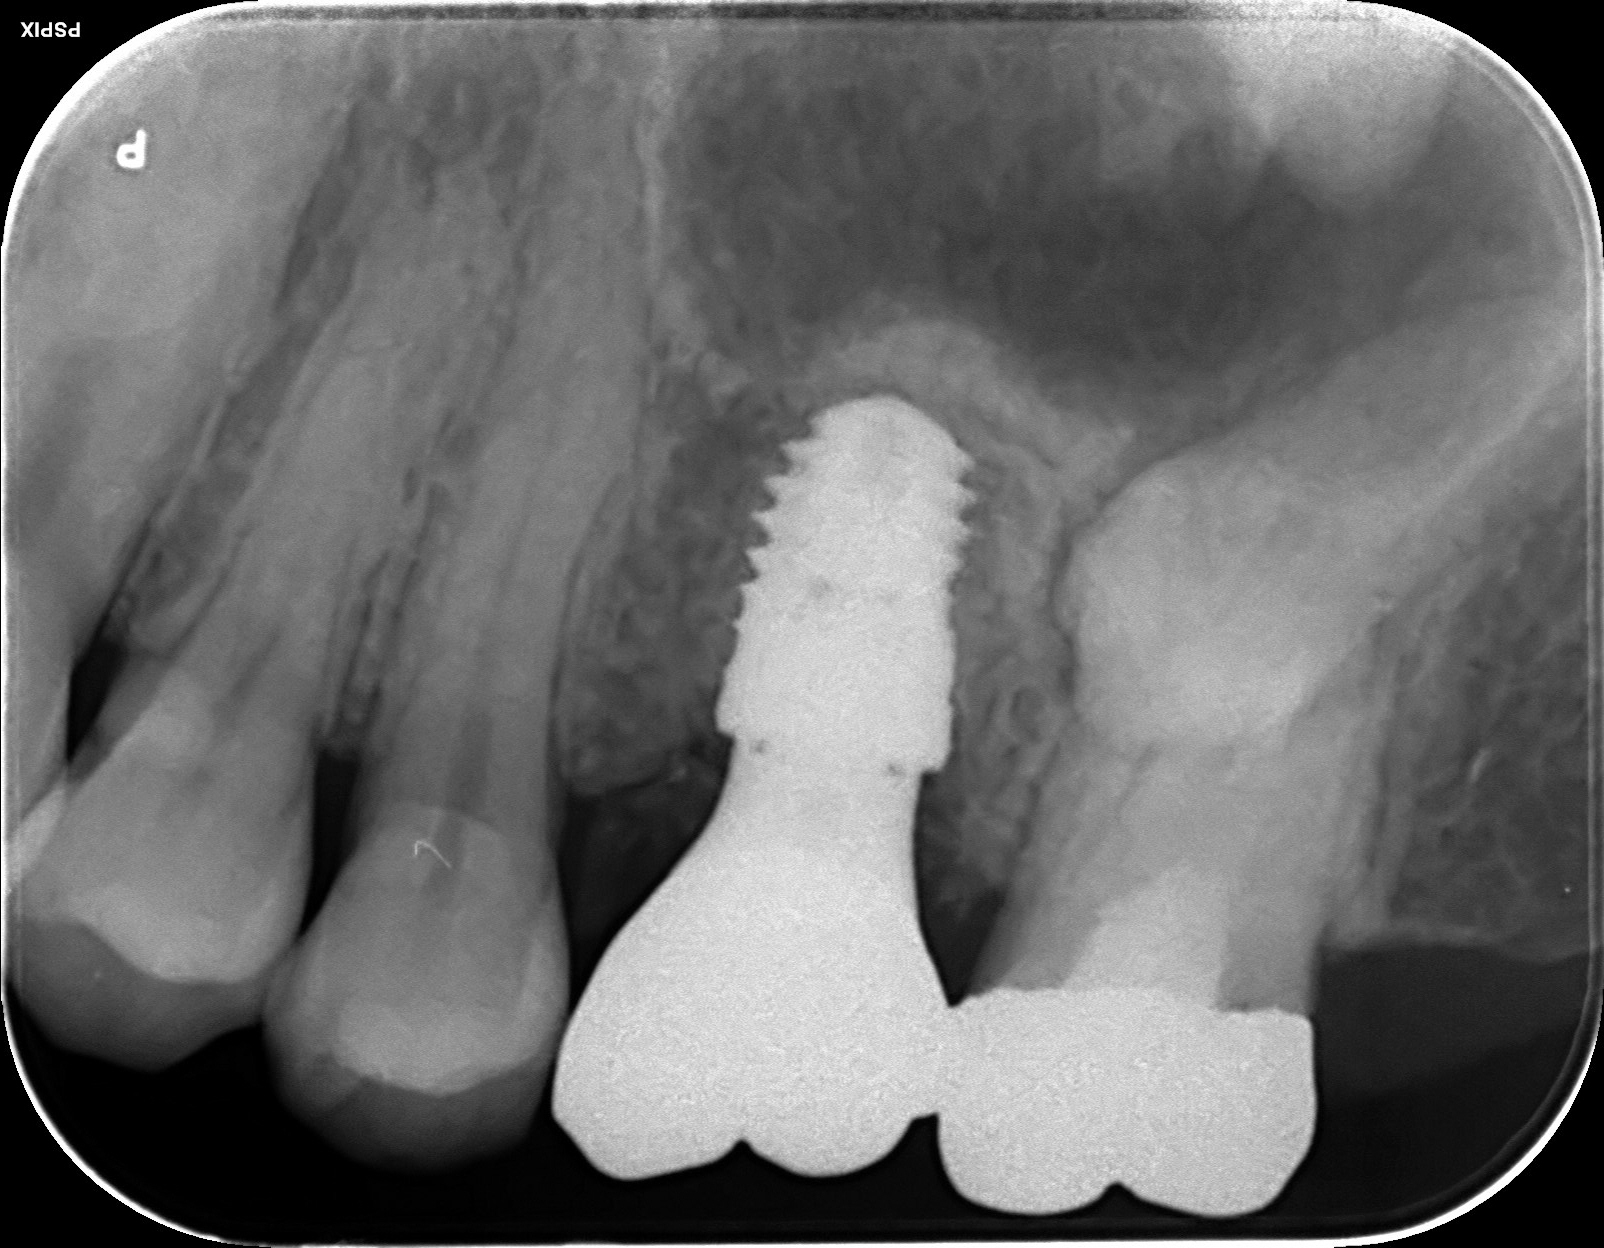

70代 女性

治療前

- 70代/女性

- 患者の具体的な症状

- 下顎の奥歯が義歯で噛みづらいため、インプラント治療を希望

- 検査方法

- コーンビームCT、レントゲン撮影

- 診断結果

- 左下6欠損

- 治療詳細

- 左下6インプラント埋入1本、骨造成なし、局所麻酔

- 通院回数

- 8回

- 治療期間

- 6か月